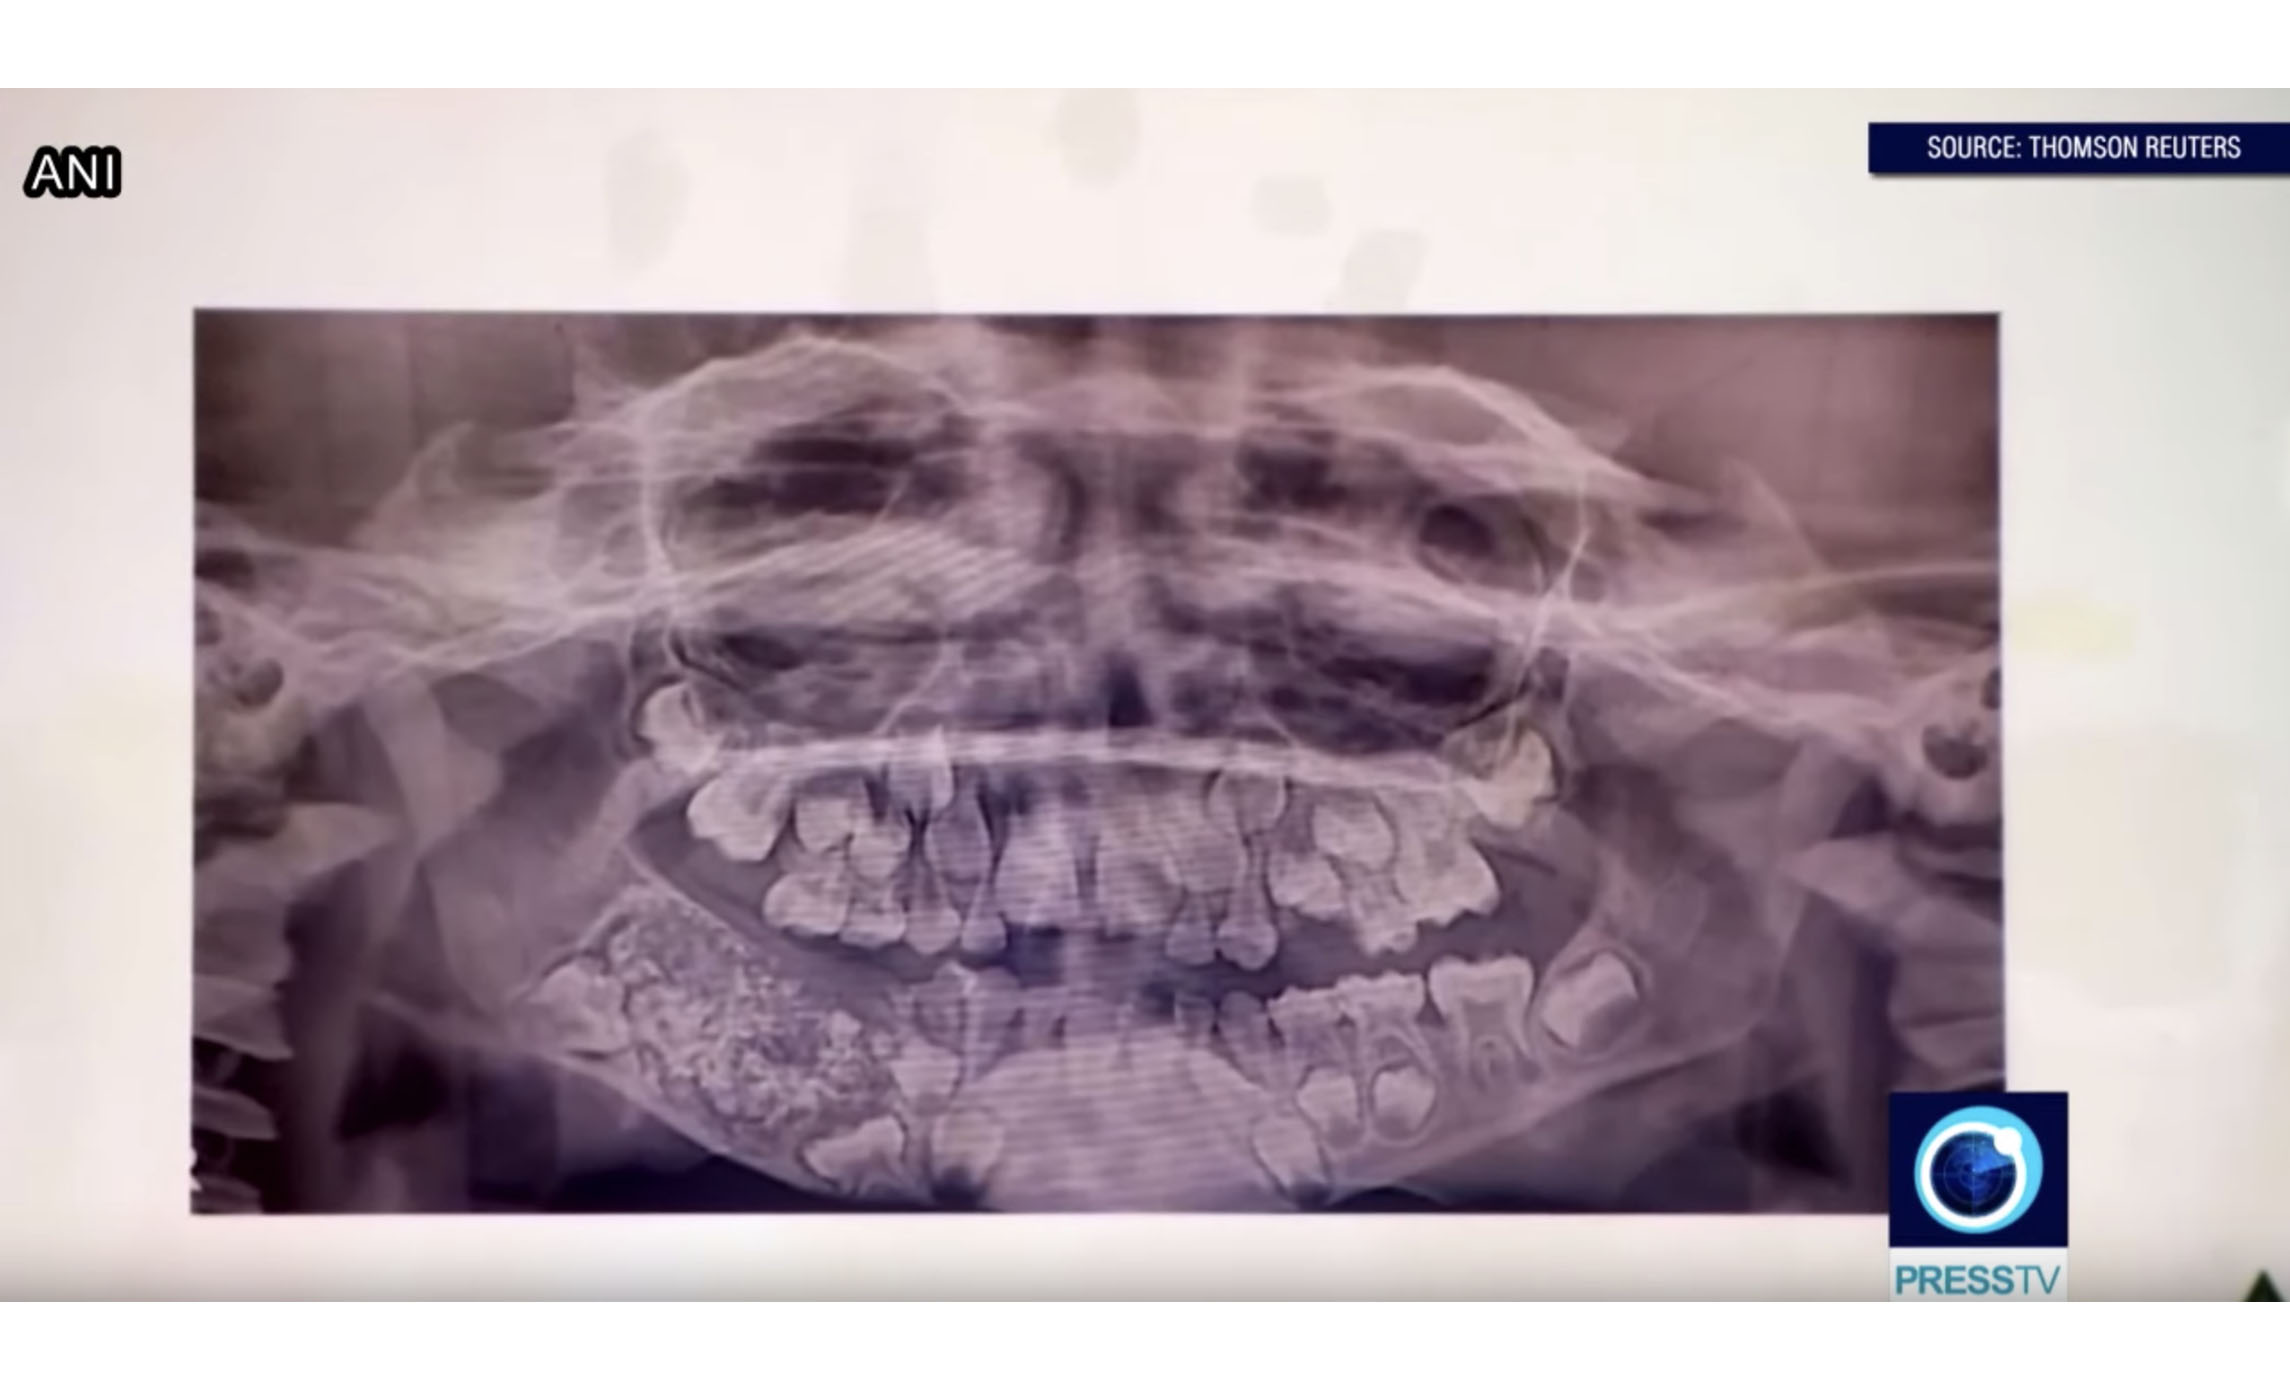

Ravindran was first admitted to the hospital in Chennai, India after intense pain and swelling in his face became unbearable. X-rays revealed the boy’s lower jaw to be filled with “abnormal teeth,” according to Dr. Prathiba Ramani, of Saveetha Dental College and Hospital.

Dental surgeons then removed the growth, which was approximately four centimeters long and three centimeters wide, and later identified it as a compound composite odontoma. “Then finally we come to know that there was 526 teeth which were present in the entire sac,” said Ravindran’s surgeon, Dr. Senthilnathan.

The teeth reportedly varied in size from very small to almost fully formed. “Even the smallest piece had a crown, root and enamel coat indicating it was a tooth,” Dr. Ramani said.